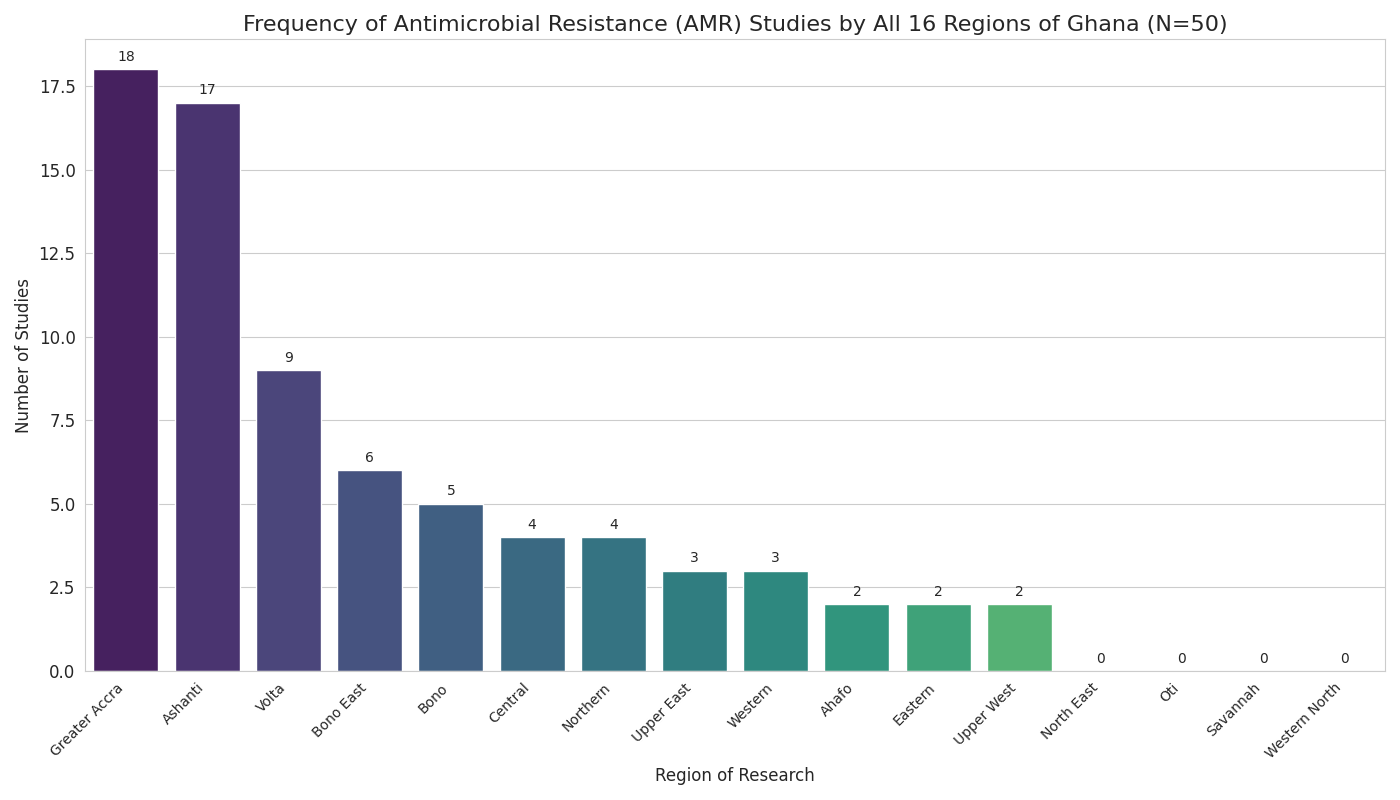

Systematic Literature Review | Nov 10, 2025

A Systematic Review Study on the Factors Contributing to Antimicrobial Resistance in Ghana

Aim: This study aimed to determine factors that contribute to antimicrobial resistance (AMR) in Ghana.

Design: This study employed a systematic...Read More